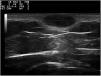

Dermoscopy revealed a uniform blue-violaceous background with no vascular structures in the interior, surrounded by a monomorphic fine pigmented reticulum (Fig. 1B). The ultrasound study revealed a subcutaneous tumor consisting of hypoechogenic areas (Fig. 2) and presenting no flow in Doppler color mode. The lesion was excised with possible suspected diagnoses of aneurysmatic dermatofibroma, microvenular hemangioma, combined nevus, and melanoma. Histology revealed a dermal nodule consisting of a proliferation of histiocytes with the presence of multiple capillaries and hemosiderophages, and bands of collagen in the periphery (Fig. 3A). The study also revealed ectasias and channels with no endothelial coating, with extravasated red blood cells and hemosiderin (Fig. 3B). Immune staining was positive for CD68 (Fig. 3C) and factor XIII, and negative for CD31, CD34 (Fig. 3D), and S100.

Ultrasound tends to show dermatofibromas as poorly defined hypoechoic areas that distort and amplify the hair follicles, which contain no calcium deposits. Under Doppler color, they tend to be hypovascular, although they may show thin arterial and venous vessels with a slow flow. Ultrasound of ADF has reported anechoic areas with no flow in Doppler color, which would correspond histologically to areas of hemorrhage. Areas of flow may also be found that would be related to vascular and cellular areas of the tumor.3–5